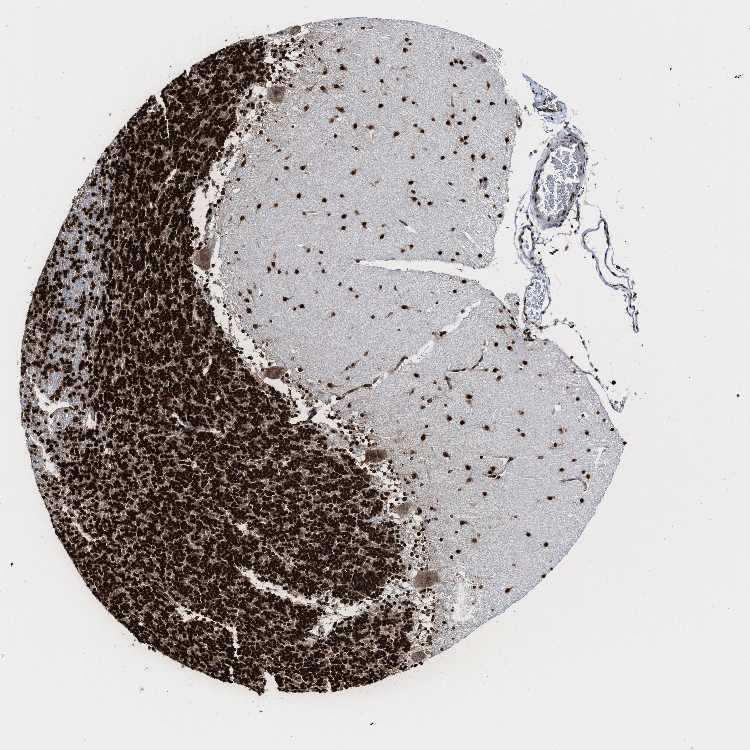

BRAIN CEREBELLUM Show tissue menu

CEREBELLUM - Expression summary

CEREBELLUM - Antibody stainingi

Antibody staining in the annotated cell types in the current human tissue is reported as not detected, low, medium, or high, based on conventional immunohistochemistry profiling in selected tissues. This score is based on the combination of the staining intensity and fraction of stained cells.

Each image is clickable and will lead to virtual microscopy that enables deeper exploration of all samples and also displays staining intensity scores, fraction scores and subcellular localization as well as patient and tissue information for each sample.

Antibody HPA019799Antibody CAB016281

Purkinje cells MediumMedium

Cells in granular layer HighHigh

Cells in molecular layer HighHigh